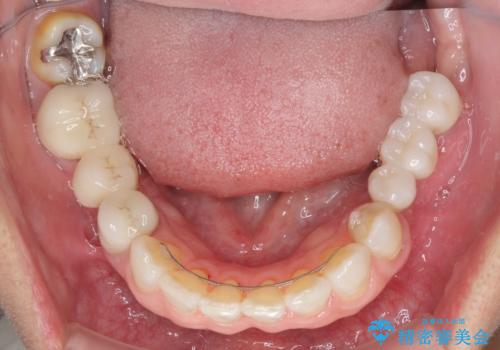

外科処置を行うため、治癒を待つ期間が数ヶ月あるため、その期間を利用して下顎前歯のスペースを矯正治療で閉じることとしました。

矯正治療までは考えていなかったそうですが、物が挟まっていた前歯のスペースがなくなり、矯正治療を行って良かったとのことでした。